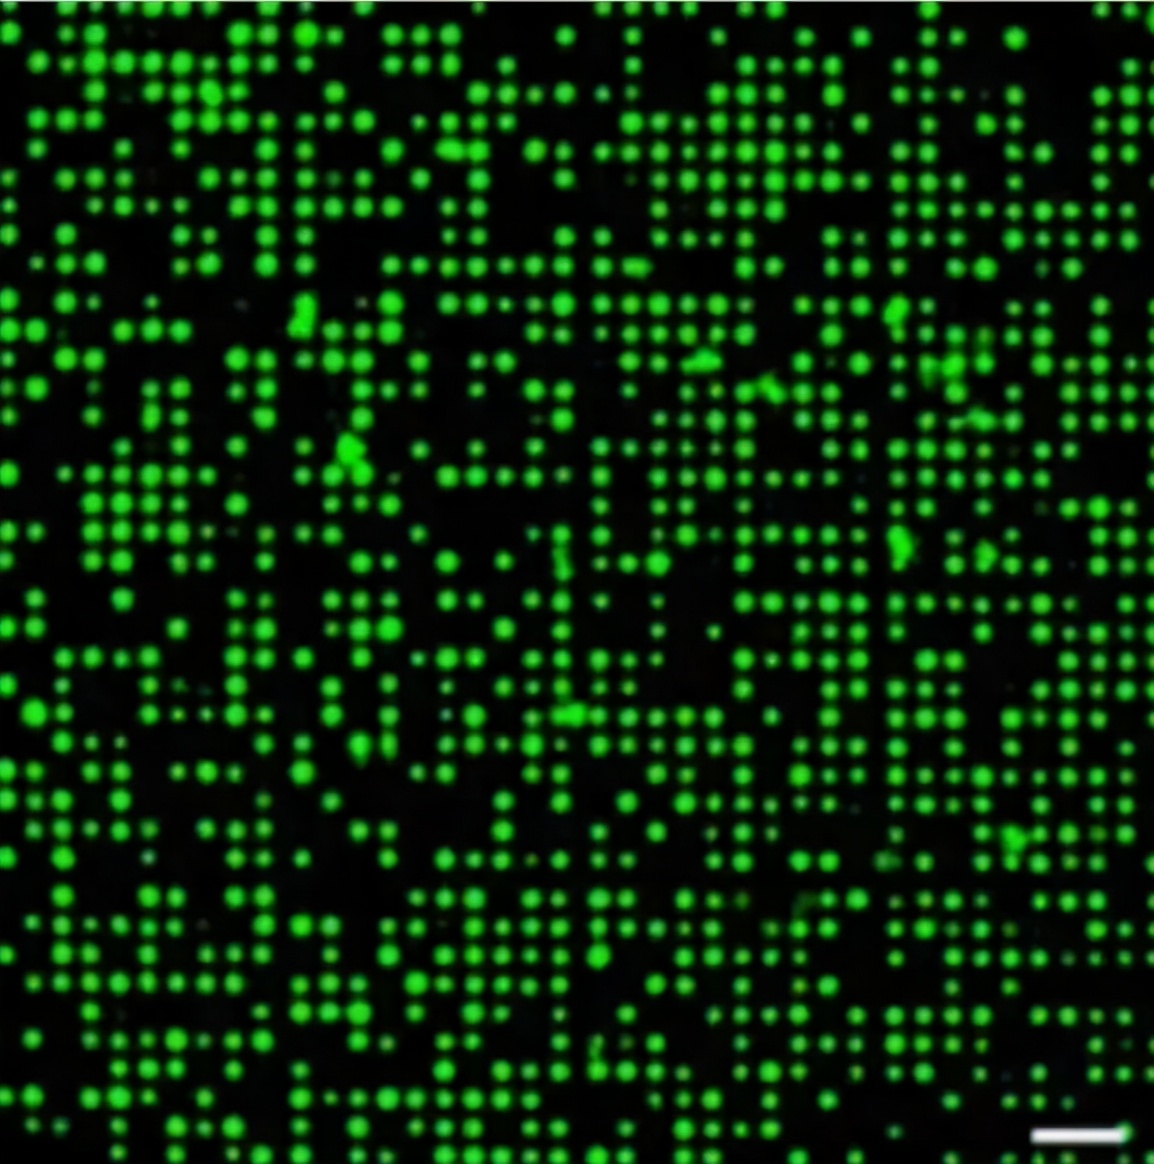

图 | 细胞排列成大规模的规则阵列(来源:受访者)

为了定位芯片上的每个单元,纳米孔膜上的微孔被划分成一个个 10×10 微孔的方形阵列,并使用数字进行标记。

例如,标记为 “4−9_J-5” 的微孔,位于纳米孔膜的第四行和第九列。也就是说,即使芯片被重新安置,任何单个细胞也都能被寻址。

此外,当这些细胞排列成大规模的规则阵列,也可为后续基因分析和细胞行为的跟踪,提供精确的单细胞分析平台。